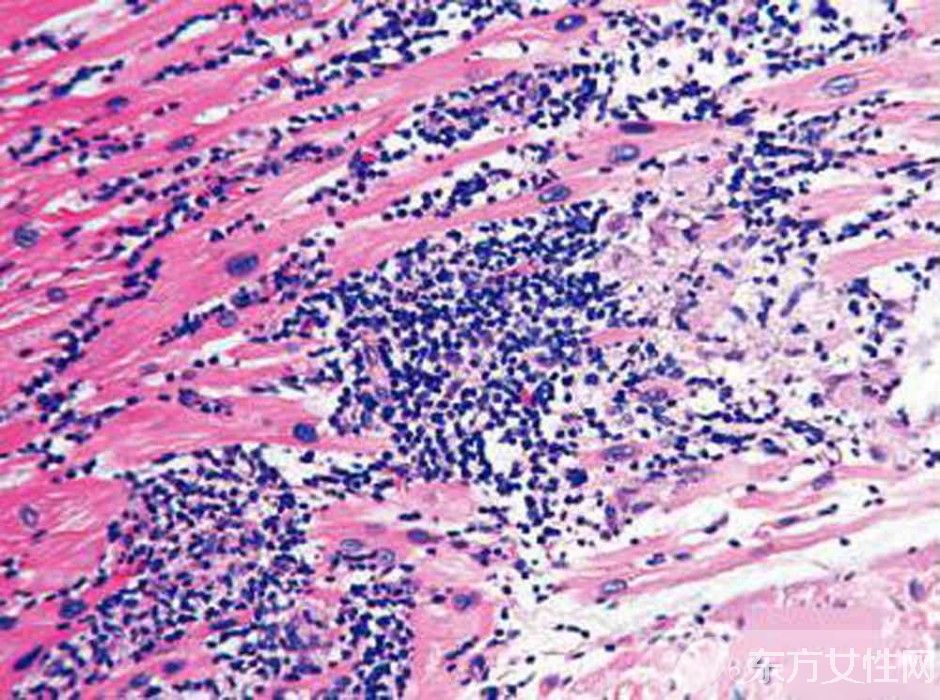

心肌炎是怎么引起的?

3、細(xì)菌感染

研究發(fā)現(xiàn),當(dāng)人體受到細(xì)菌和病毒混合感染時(shí),可能起協(xié)同致病作用。還有在妊娠期間,妊娠可以增強(qiáng)病毒在心肌內(nèi)的繁殖,所謂圍產(chǎn)期心肌病可能是病毒感染所致。